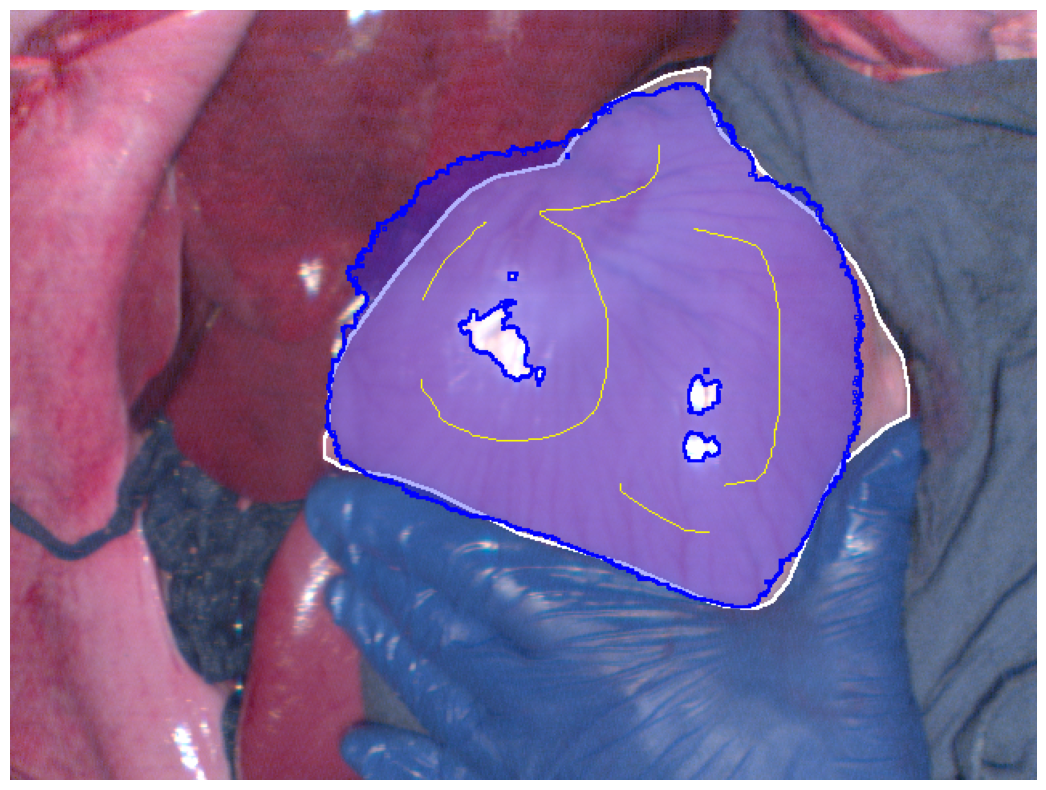

(b) Hyperspectral image best Dice segmentation result

Figure 2: Segmentation results (blue regions) at the best Dice coefficient for different methods and ground truth (white regions), along with the curves of Dice coefficient variation with threshold adjustments.

In Fig. 2, the segmentation results at the best Dice for the four different methods are displayed, along with the variation in Dice coefficients with threshold adjustments. From Fig. 2e, it can be seen that the Euclidean distance method has the lowest maximum Dice score of 0.914. The methods using geodesic distance maps generated from hyperspectral images and reconstructed RGB images achieve similar maximum Dice values, both higher than the Euclidean method. The deep learning-based feature geodesic distance map method achieves the highest maximum dice coefficient.